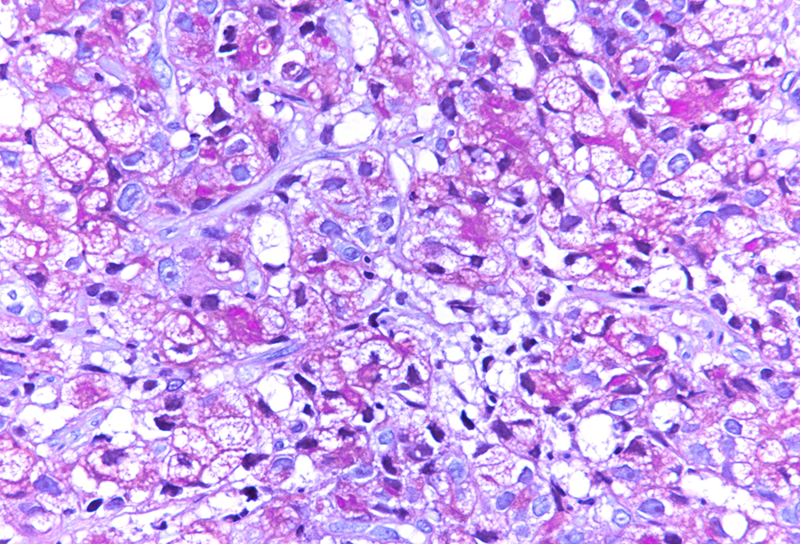

Gastric biopsy from a patient with liver cirrhosis.

Poorly cohesive (“diffuse”) gastric adenocarcinoma with foamy (histiocyte-like) cells.

Histologically, we saw two biopsy pieces with gastric mucosa. On the first one, there was a normal corpus mucosa with no inflammation, no atrophy and no intestinal metaplasia. However, on the second one, there was a dense infiltrate of cells with ample foamy cytoplasm, yet only slightly enlarged, hyperchromatic nuclei, which were placed either centrally or eccentrically, that is, close to the cellular membrane. Occasional classical signet ring cells were also present (Panels A-B). The foamy cells were weakly positive for PAS (Panel C), albeit diffusely positive for pankeratin (Panel D). We performed some additional stains: The foamy cells were positive for MUC5AC (Panel E) and MUC6 (Panel F), while negative for MUC2 (not shown). A final diagnosis of poorly cohesive (“diffuse” according to Lauren) gastric adenocarcinoma with foamy (histiocyte-like) cells.

The presented case demonstrates tumour cells, which could easily be mistaken for histiocytes, in particular since classical PAS-positive signet ring cells were only focally present. As in a benign histiocytic proliferation, e.g. in a xanthelasma, the nuclei of the tumour cells were not markedly enlarged, often centrally placed, still slightly irregular and hyperchromatic. The keratin stain definitively made the diagnosis.